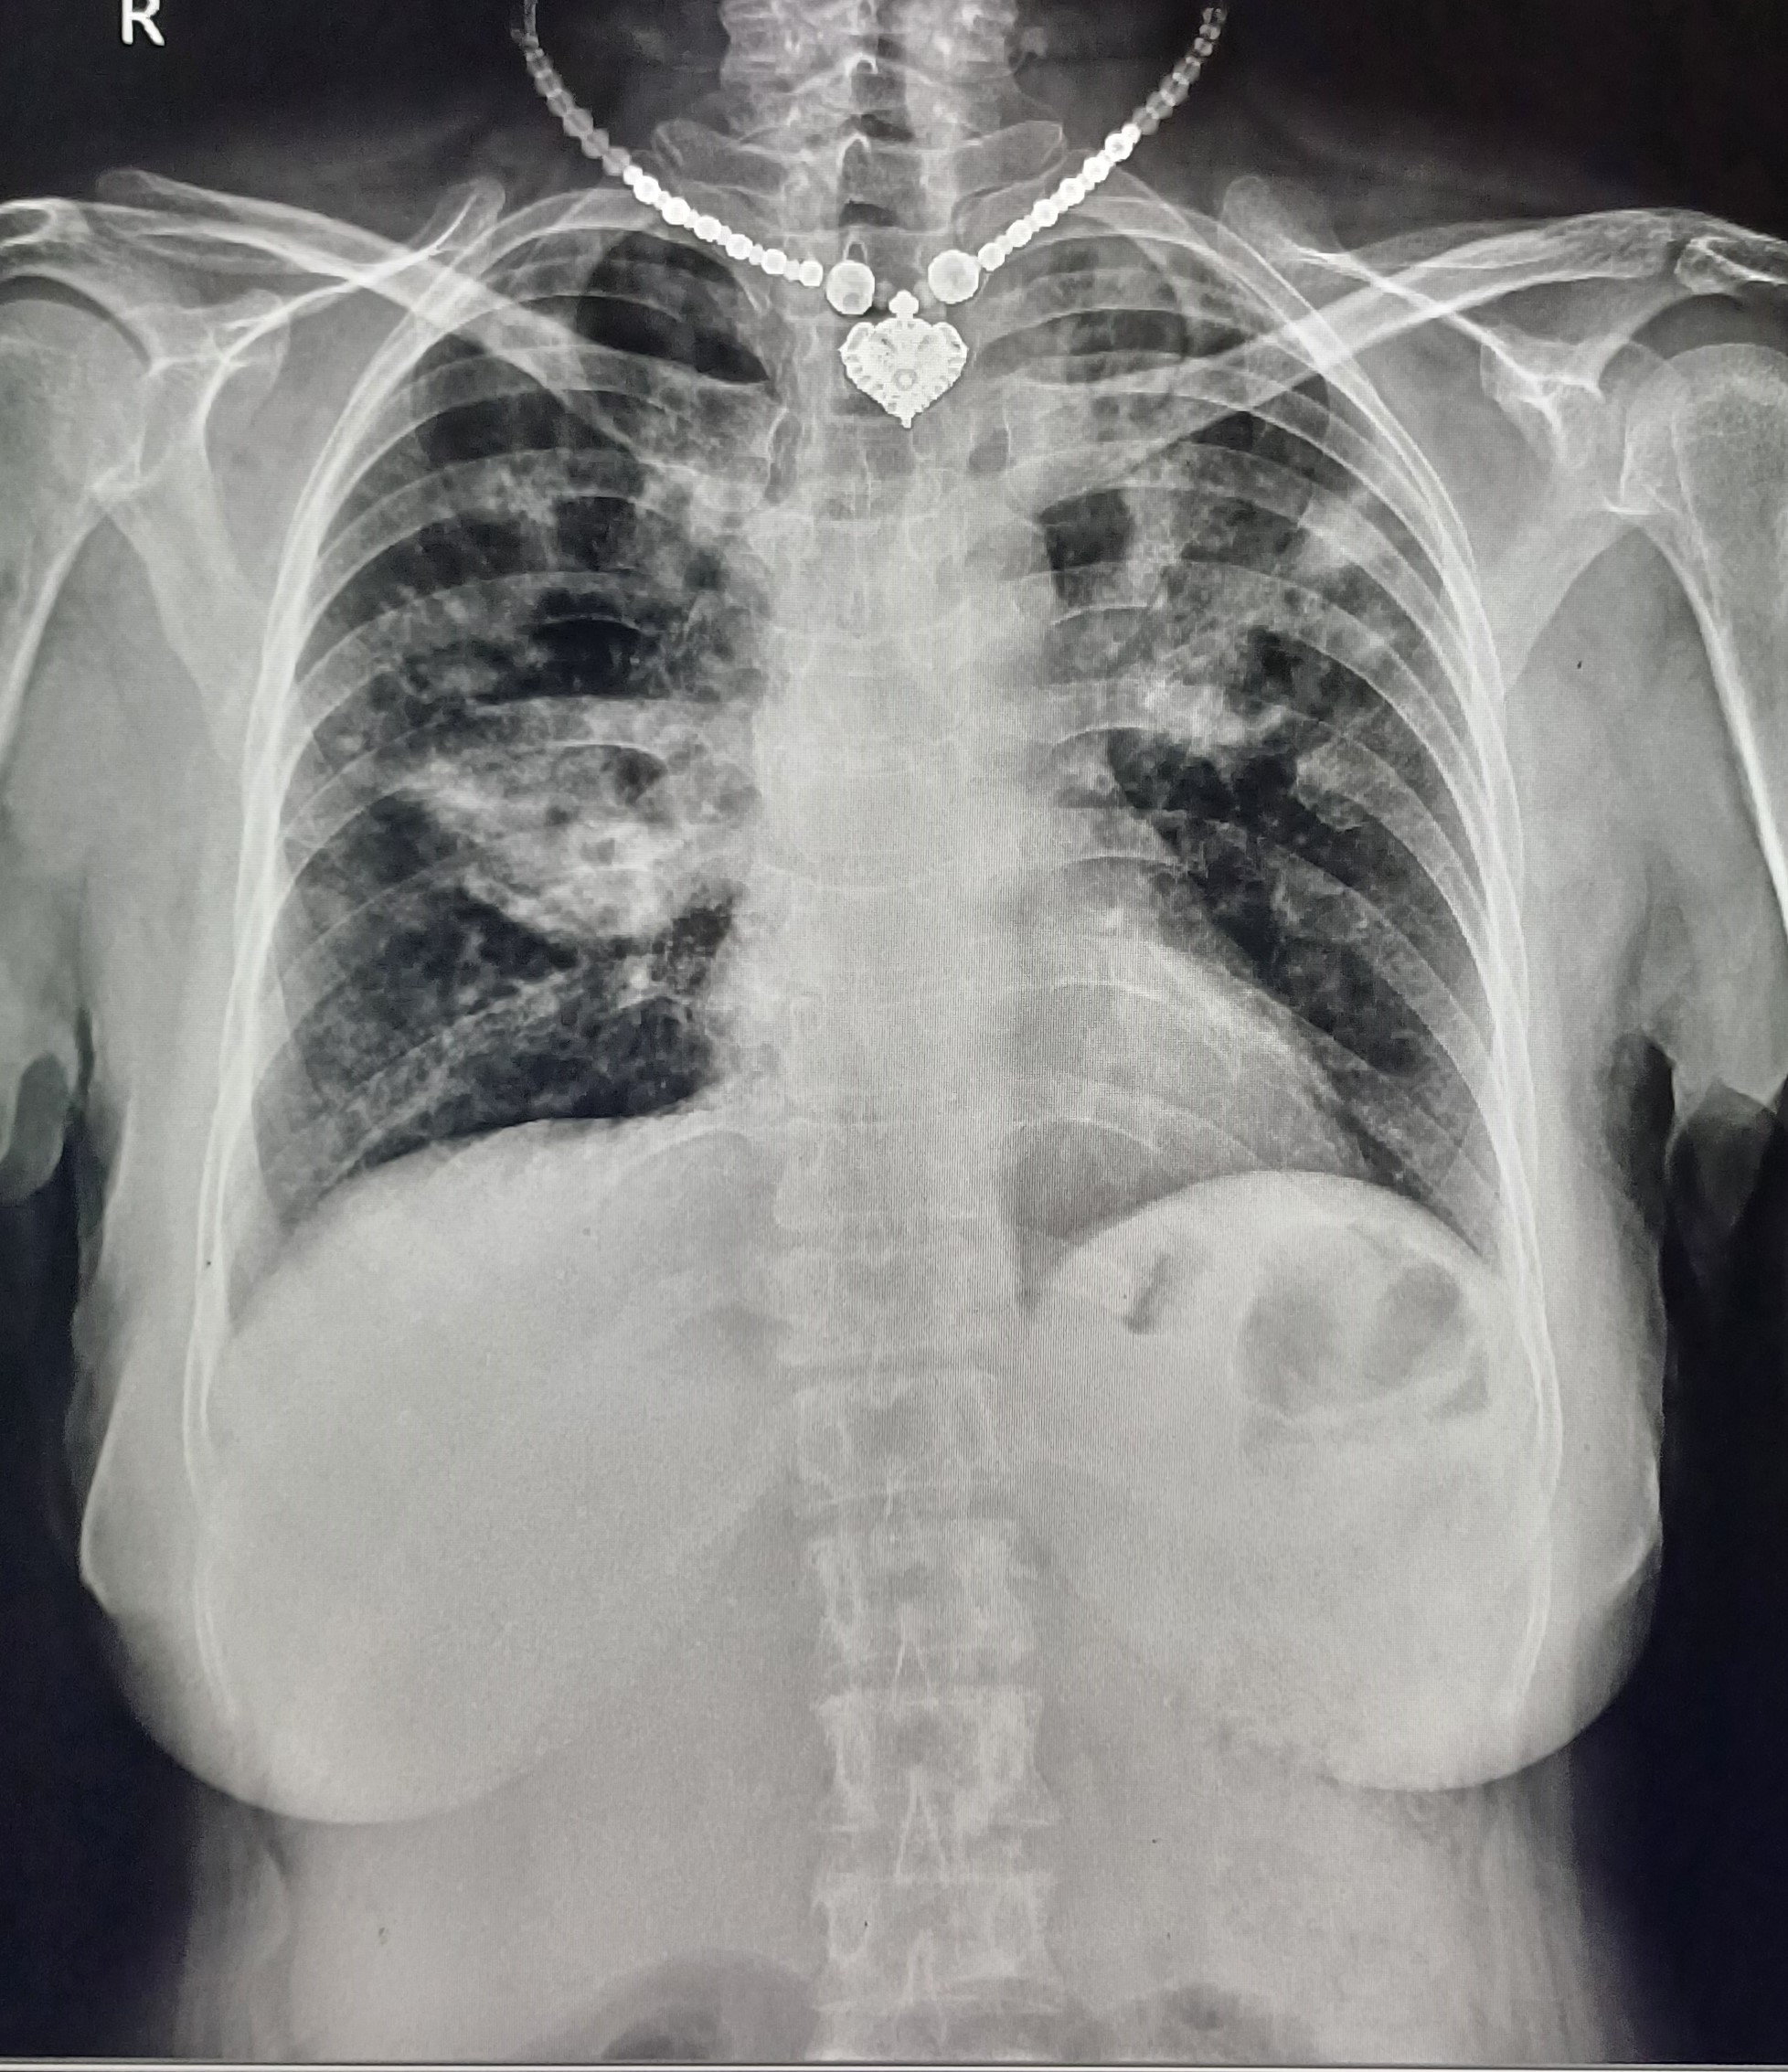

| 24 | IGGMC, Nagpur, Nagpur | P2 | 29-4448 | Atul Borkar | Consent taken on Paper | 42 Yrs. |

Provisional Diag : Tubercular Pleural Effusion

Final Diag : Pulmonary Tuberculosis With Tubercular Pleural Effusion (Microbiologically Confirmed PTB) |

TB Case (Confirmed) | left-sided homogeneous opacity with the trachea shifted to the right, along with ill-defined infiltrates | Abnormality visible on x-ray |

View |

|||